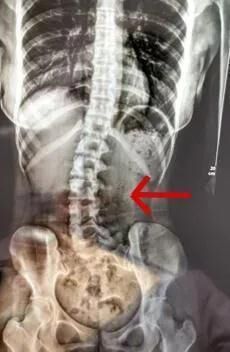

“正值18岁的女生小邹(化名),经常因腰痛、脖子酸等症状,并且情况逐渐严重。于是来到医院就诊,医生检查发现脊柱严重侧弯,经过x光检查,发现她的腰椎向右侧弯、旋转,并以腰2椎体为中心向右侧弯,脊柱向右发生明显侧弯。”

d2.jpg 小邹的脊柱明显侧弯 广医三院图医生经过问诊后发现竟是因为 她的睡眠姿势不对。小邹长时间侧躺睡而且是侧同一边,并且下腿摆姿不正确。“患者是因为其睡姿不当,原有正常的脊柱体态在日积月累的错误睡姿中逐渐失衡,骨盆与脊柱位置变化,脊柱就发生了侧弯。”广州医科大学附属第三医院中医科主任医师胥海斌介绍。